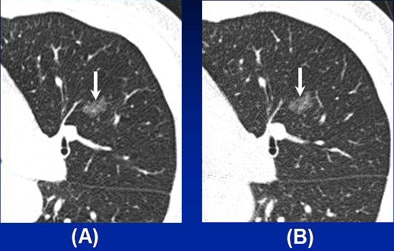

Patients with malignancy were significantly older than those with benign lesions (57.83 ± 8.57 years versus 52.19 ± 10.71 years, p = 0.005). Unlike the Ferretti study, but in line with most previous research, the size of malignant lesions was larger than that of benign lesions (10.37 ± 5.74 mm versus 7.93 ± 5.01 mm, p = 0.026). Lesion size 8 mm or larger was determined to be the optimal threshold for differentiating malignancy and benignity with balanced sensitivity and specificity.

In addition, malignant lesions were more likely to show pleural retraction, bubble lucency, or air bronchogram (p = 0.035). Significant associations between malignancy and patient age (odds ratio, 1.061), lesion size 8 mm or larger (odds ratio, 2.784), and the presence of pleural retraction, bubble lucency, or air bronchogram (odds ratio, 4.414) were found. With these characteristics, the differentiating performance of multiple logistic regression models was relatively good (area under the curve [AUC] = 0.762).

"There was a significant difference between patients with malignant pnGGO and those with benign pnGGO in terms of patient age," Park said. Other significant differences between malignant and benign pnGGOs were seen in lesion size and the presence of pleural retraction. "Size larger than 8 mm was an independent estimator of malignant and benign pnGGOs," he said.